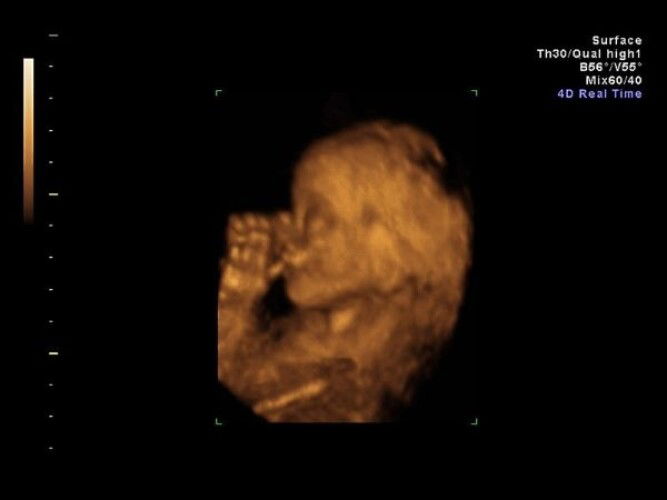

What are the benefits of 3D ultrasound during pregnancy?

Read more about it here: <a href='https://sg.theasianparent.com/3d-ultrasound-tests-everything-you-need-to-know-about-it' target='_blank' >https://sg.theasianparent.com/3d-ultrasound-tests-everything-you-need-to-know-about-it</a>